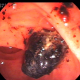

A 63 year male diabetic patient had complaints of pain abdomen with radiation to the back.He was investigated with MRCP showing a 5mm main pancreatic duct with stone in the neck and upstream dilatation.The pancreas was atrophic.CBD,GB were normal.